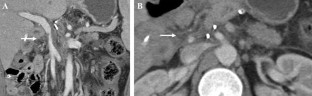

Fig. 1

Fig. 2